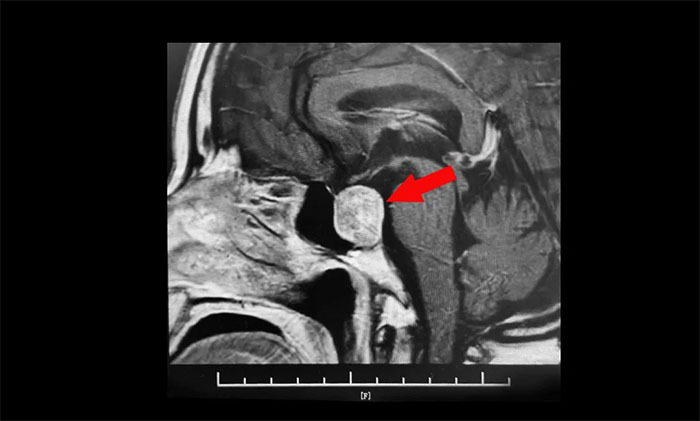

鞍區(qū)MRI平掃+增強(qiáng)顯示:蝶鞍顯著擴(kuò)大,鞍區(qū)見(jiàn)腫塊信號(hào),大小約29*19*24mm;垂體柄明顯縮短左偏;病變向鞍上生長(zhǎng),占據(jù)鞍上池,推移視交叉;向鞍旁生長(zhǎng),侵及右側(cè)海綿竇,右側(cè)海綿竇內(nèi)頸內(nèi)動(dòng)脈被推壓、包繞,右側(cè)頸內(nèi)動(dòng)脈海綿竇段較對(duì)側(cè)稍細(xì)。

▲ 腫瘤侵襲生長(zhǎng),包繞頸內(nèi)動(dòng)脈,knosp分級(jí)Ⅲ級(jí)